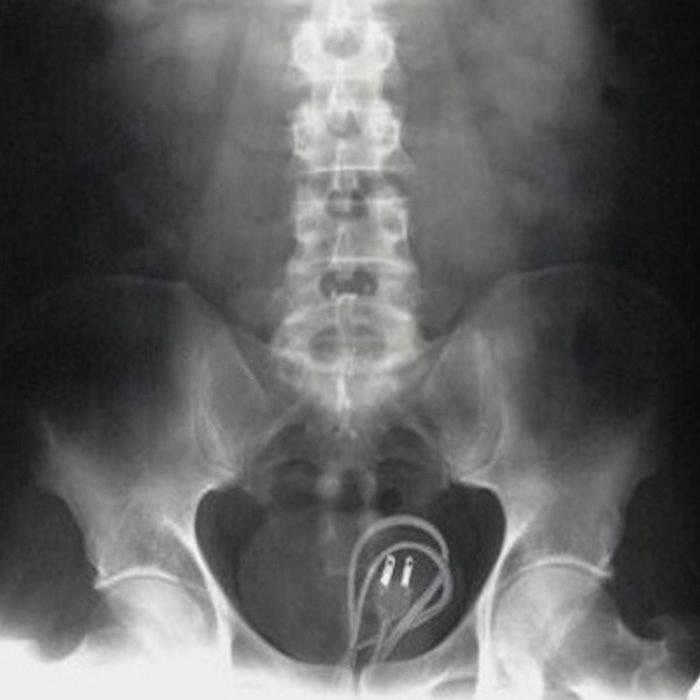

▼不知道為什麼看到這圖的時候,有一瞬間閃過我的充電線在哪的念頭...

圖片來自:ems1